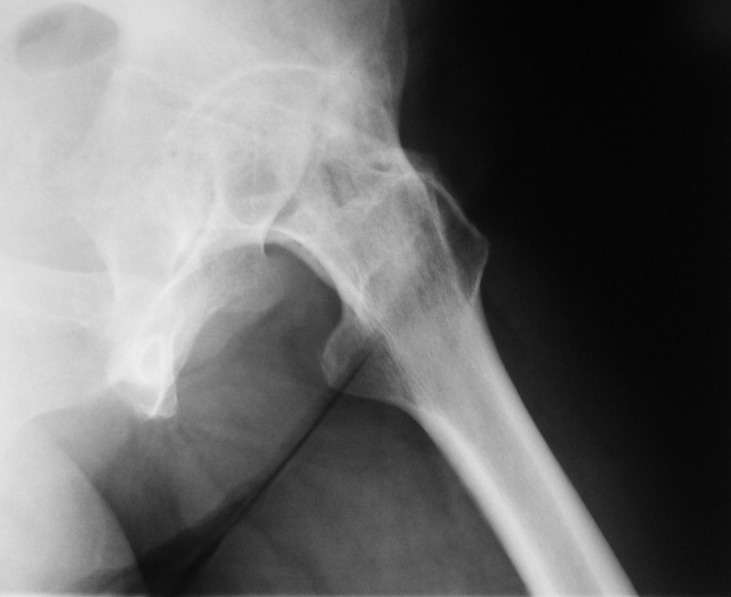

При обследовании выявлен анкилоз тазобедренного сустава в приведении. Видимо, в период пребывания в тяжелом состоянии появились гетеротопические оссификаты. За исключением того, что осталась одна почка, сейчас других медицинских проблем нет.

Пациентку в первую очередь беспокоят боли в спине, на отсутствие движений в суставе она вроде и не жалуется. Вопрос насчет тактики. Корсет и анальгетики вряд ли решение. Первый вариант - удаление оссификатов и эндпротезирование, второй - корригирующая остеотомия в проксимальном отделе с устранением порочного положения.

Боли в спине обусловлены порочным положением бедра. Эндопротезирование более интересно, т.к. дает еще и движения в суставе (кроме устранения порочного положения). Оссификаты не страшные, а учитывая срок (3 года) - уже созревшие. Я зарекся делать ЭТС при больших оссификатах - очень частый рецидив даже на фоне индометацина и луч.терапии.

Я думаю, что эндопротезирование - более предпочтительный вариант у пациентки 53 лет. К тому же суставная щель прослеживается и, вероятнее, большой сложности с установкой вертлужного компонента не будет. Высока вероятность необходимости аддуктотомии.

В любом случае замена сустава после оссификации дело не благодарное - безболезненная контрактура станет болезненной контрактурой.

После корригирующей остеотомии сохранится чрезмерная нагрузка на поясничный отдел за счёт анкилоза т/бедр. сустава.На фоне остеохондроза,спондилёза,спондилоартроза и спондилолистеза устранение порочного положения не избавит от болей и вряд-ли даже уменьшит их.Мне кажется тут нет альтернативы эндопротезированию.Но даже в этом случае не исключено,что позднее, на повестке появится необходимость вмешательства на позвоночнике.